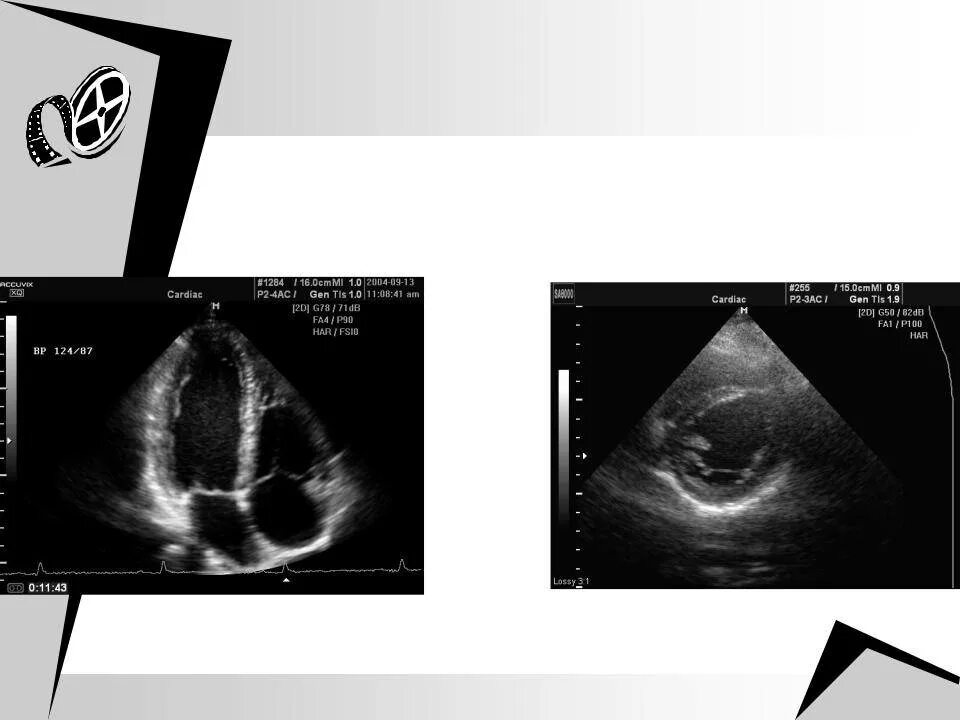

Дополнительная хорда мкб